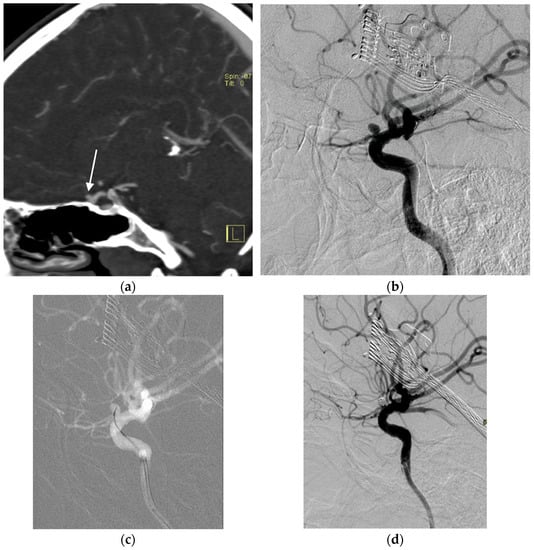

2.3. Aneurysms

2.4. Tumors